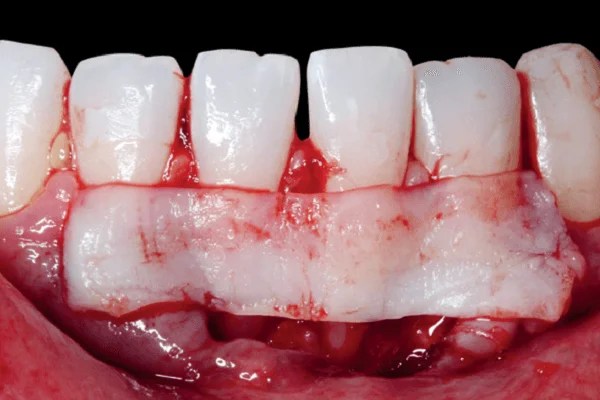

Les interventions chirurgicales comprennent la chirurgie d’accès pour accéder aux zones infectées, les greffes osseuses pour régénérer l’os perdu, le recouvrement radiculaire pour couvrir les racines exposées, l’augmentation du volume gingival pour améliorer l’esthétique, la régénération guidée des tissus pour encourager la croissance cellulaire appropriée, et la chirurgie plastique parodontale pour des fins esthétiques